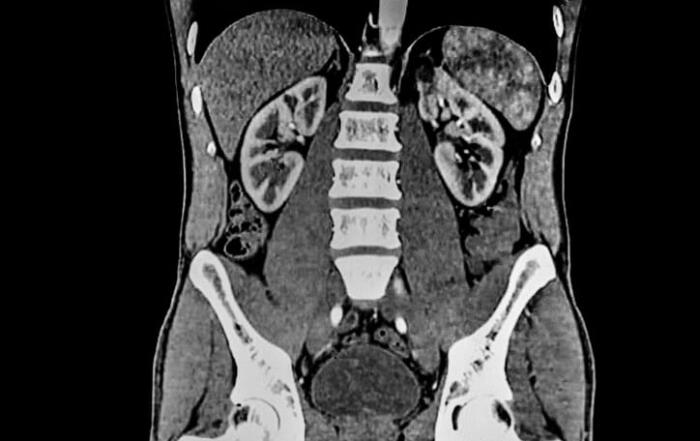

This low dose Computed Tomography (CT) scanner from Siemens Healthineers provides exceptional image of the inside of a patient’s body with minimal radiation.